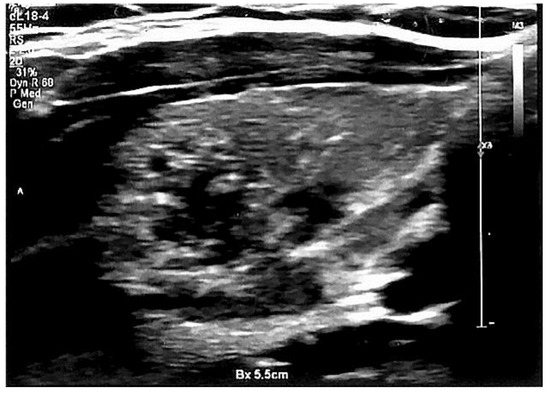

2.3. Thyroid Imaging—Ultrasonography and Elastography